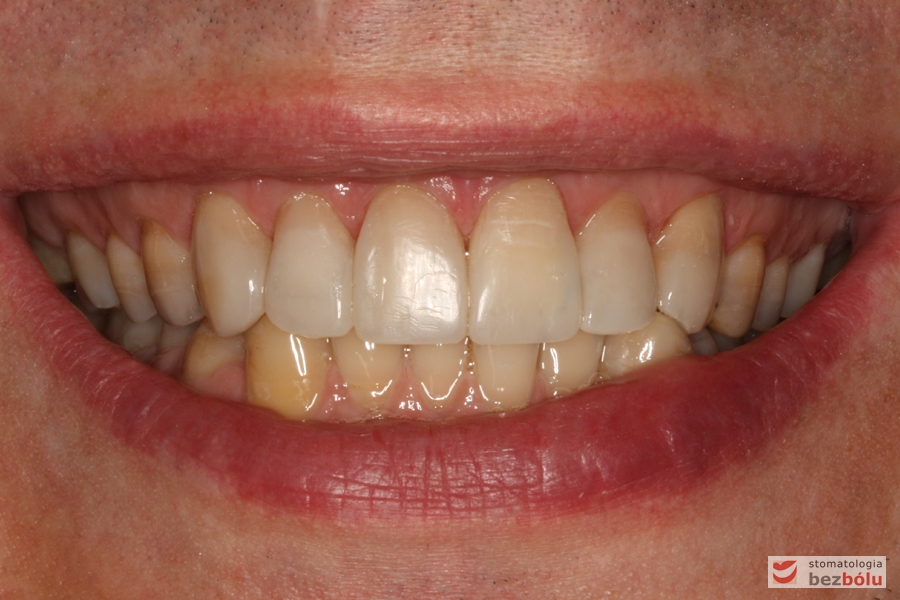

Uśmiech pacjenta przed leczeniem

Uśmiech pacjenta po leczeniu - radość i satysfakcja

Uśmiech pacjenta po leczeniu – radość i satysfakcja